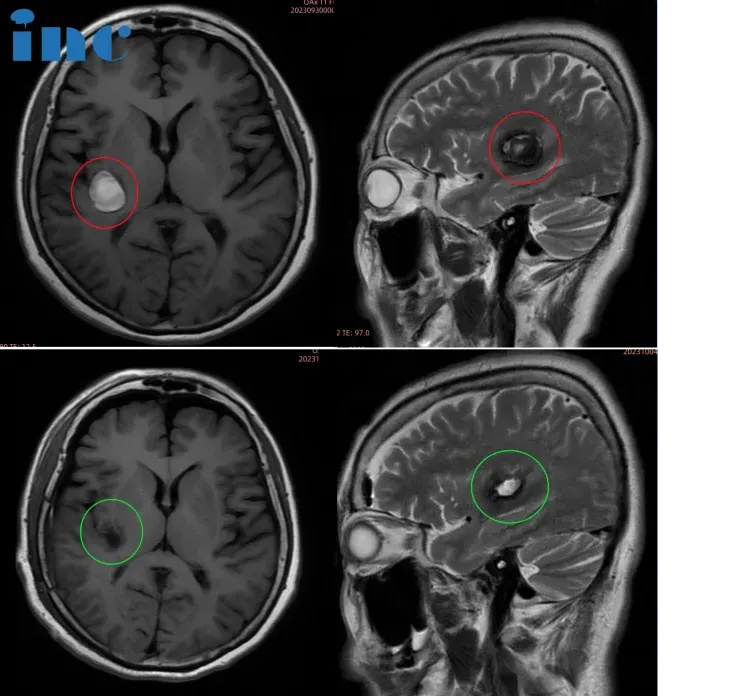

脑膜瘤患者采访

52岁女性—CPA区脑膜瘤

”我们之前也跑了很多地方。发现一个病灶以后,我们走了很多地方,很多医院认为手术风险很大,有些医院根本就没办法做手术。好的医院回复做下来以后较大的困难较大的问题是有后遗症,就是可能出现其他症状。二个就是切除不干净,那对我们来说这个情况就比较麻烦,所以一直在等。

我一直在这手术室外面等着,我爱人手术室出来以后,眼睛睁着,还要讲话那种……不像一个从这么重症手术出来的这么一个人,这个脸部好像各方面,就是我们原来从其他医院评估的这种症状都没有。她出来以后很清醒,在ICU里面就清醒,在里面状况就好。肿瘤基本上切除了,从我来讲能达到这个水平是开心的。“